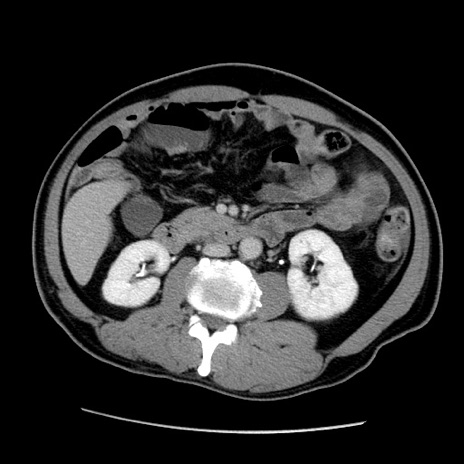

症例22(横断像)

【症例】50歳代男性

【主訴】腹痛

【現病歴】AVMからの被殻出血のため回復期リハ病棟入院中。 本日午後3時頃急に下腹部痛が出現した。

【既往歴】AVM、被殻出血、虫垂炎、高血圧

【身体所見】意識晴明、左半身不全麻痺、会話の理解は良好、36.5°C、腹部:膨隆、全体に板状硬、下腹部正中に圧痛点あり、反跳痛-、筋性防御不明、右下腹部にope scar

【データ】WBC 9400、CRP 0.06